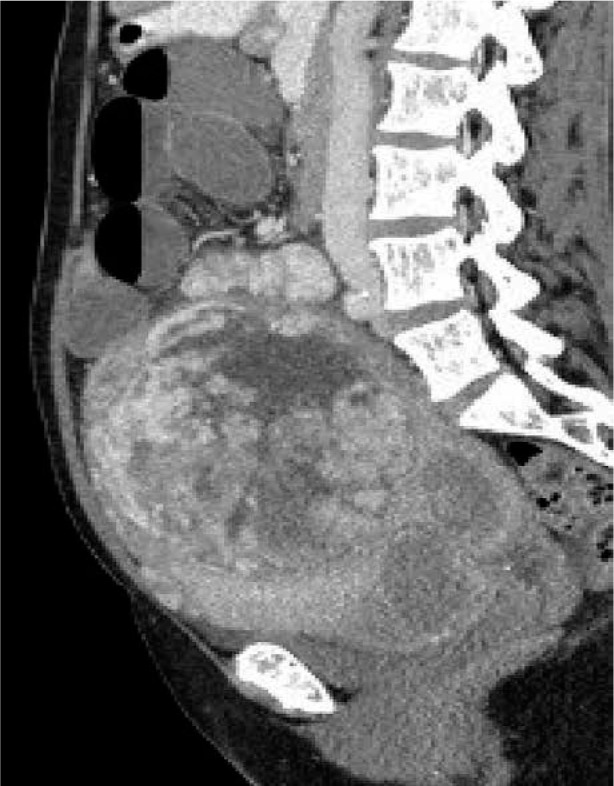

小肠梗阻(SBO)是一种严重的疾病,有明显的症状,如便秘、呕吐和腹胀。它通常是由公认的因素引起的。成像技术和微创手术的最新进展大大提高了我们准确选择手术干预患者和迅速识别常见SBO原因的能力。然而,认识到诊断罕见的SBO病因仍然是一项挑战,这一点至关重要。我们报告一个罕见的病例机械性肠梗阻由巨大的子宫肌瘤引起的44岁妇女。大子宫肌瘤可引起机械性小肠阻塞,虽然这不是常见的原因。诊断成像,特别是计算机断层扫描,在诊断和确定适当的管理计划中起着至关重要的作用。准确的监测和成像可以通过避免不必要的手术干预和降低发病率和死亡率来改善患者的预后。治疗方法包括内科和外科两种。这两种方法都被证明是有效的,如果药物治疗不成功,外科手术是最后的手段。这些手术方法的准确性和有效性已显示出良好的结果和显著的预后益处。识别和报告罕见的肠梗阻原因对于提高未来的认识和提高患者的预后是至关重要的。

Small bowel obstruction (SBO) is a serious condition with distinct symptoms such as constipation, vomiting, and abdominal distension. It is commonly caused by well-recognised factors. Recent advancements in imaging techniques and minimally invasive procedures have significantly improved our ability to accurately select patients for surgical intervention and promptly identify common SBO causes. Nonetheless, it is crucial to recognise that diagnosing rare SBO causes remains a challenge. We present a rare case of mechanical bowel obstruction caused by massive uterine fibroids in a 44-year-old woman. Large uterine fibroids can cause mechanical small intestine obstruction, although this is not a common cause. Diagnostic imaging, particularly computed tomography, plays a crucial role in diagnosing and determining appropriate management plans. Accurate monitoring and imaging can lead to improved patient outcomes by avoiding unnecessary surgical intervention and reducing morbidity and mortality rates. Treatment options include both medical and surgical methods. Both approaches have proven effective, with surgical procedures being the last resort if medical treatments are unsuccessful. The accuracy and efficacy of these surgical methods have shown promising results and significant prognostic benefits. It is critical to identify and report rare causes of bowel obstruction to improve future recognition and enhance patient outcomes.